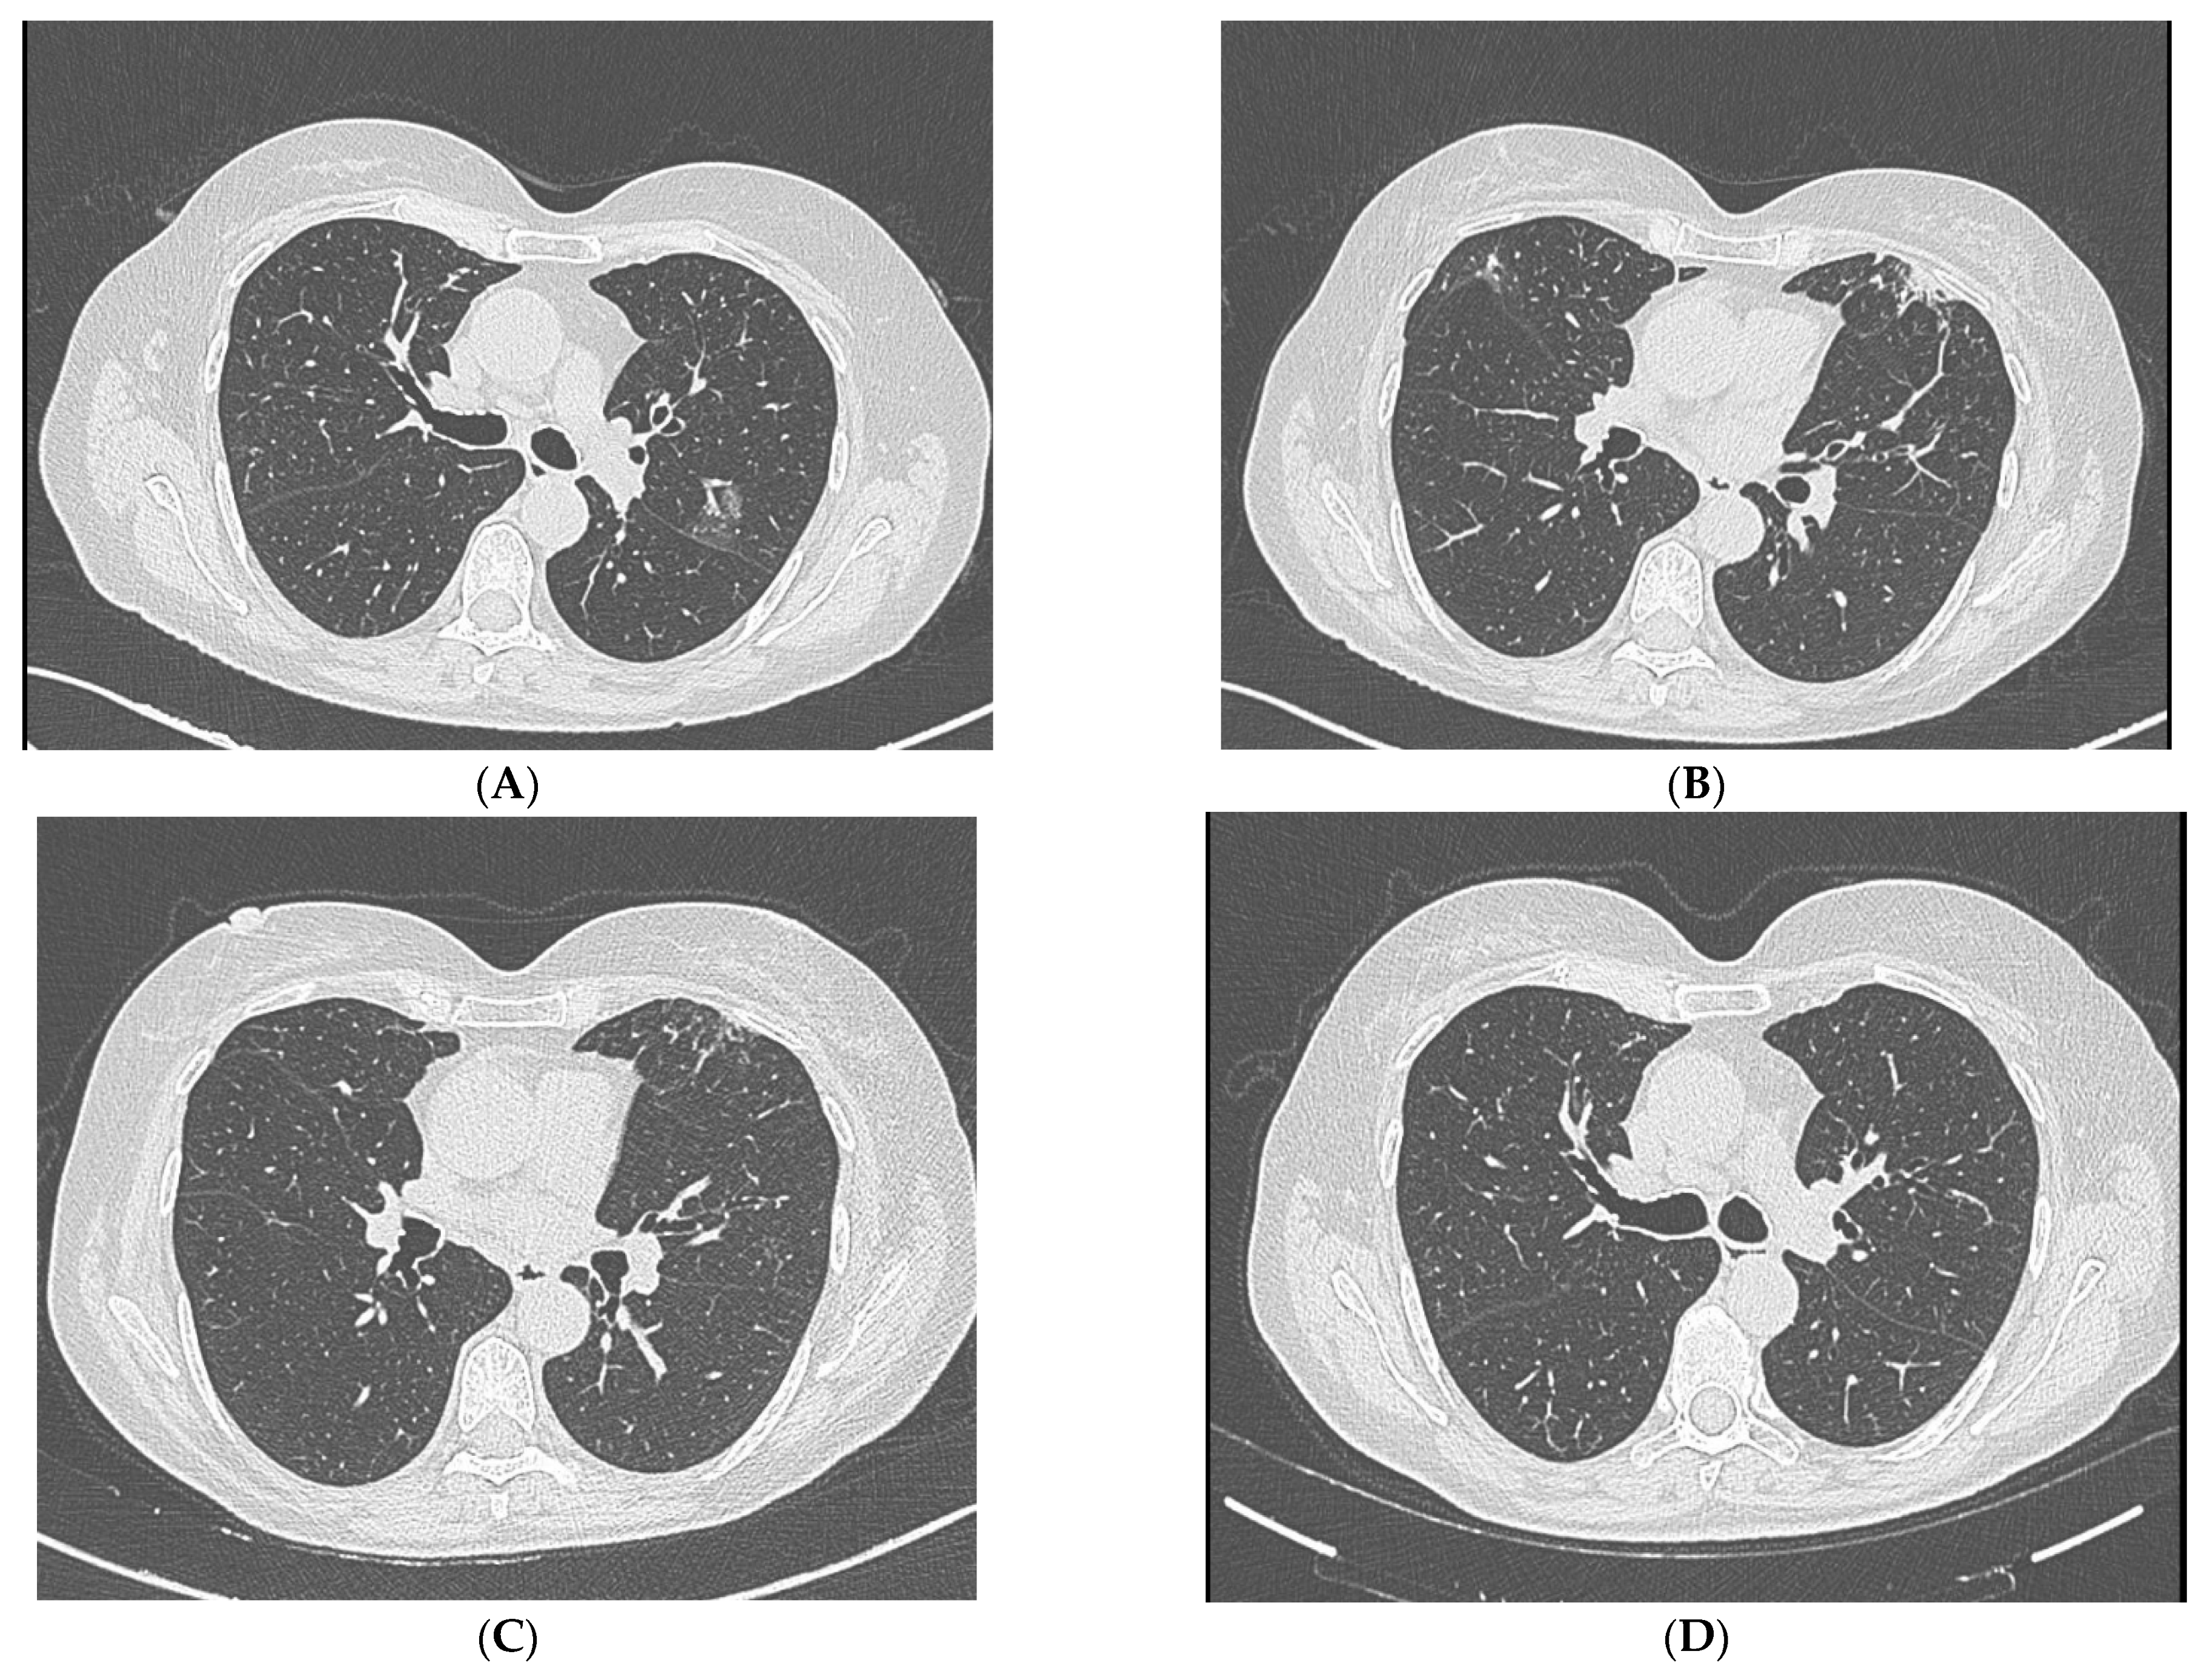

4. Diagnostic Studies

5. Clinical Course